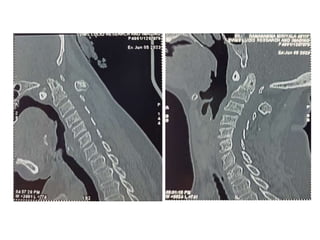

M Ramanamma is a 48-year-old female who presented with neck pain and paresthesias in her limbs for the past 5 months. On examination, she had decreased strength in her right upper and lower limbs and hypertonia in her lower limbs. Imaging showed atlantoaxial dislocation with compression of the cervical spinal cord at C1-C2, explaining her symptoms.